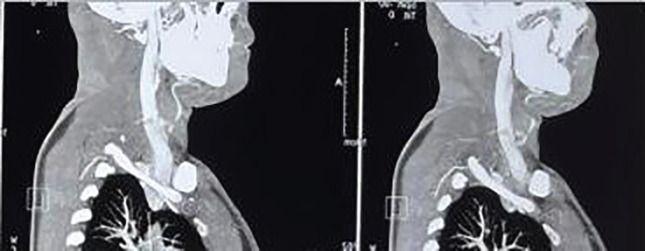

Airgun injuries are prevalent in the pediatric population. The present study described a case of air gun pellet injury to the left carotid artery and its successful management. A 25-year-old man presented to the emergency department complaining that his son had accidentally injured him with an air gun pellet while playing. The X-ray cervical spine revealed a single foreign body (pellet) located directly anterior to the C5-C6 vertebra. A CT angiography of the neck showed a spherical hyperdense object just anterior to the C6 vertebral body on the left side, 3 mm posteromedial to the left common carotid artery, which was most likely a pellet foreign body. The patient was sent to operation theatre (OT) for exploration. There was a rent in the internal carotid artery with active bleeding. After exerting both proximal and distal control, the rent was closed. Close air gun injury could result in gunshot wounds, as in the present case. Plain X-rays in AP and lateral view are required. Nonoperative management could be employed in a restricted group of patients with satisfactory outcomes. Those who have vascular involvement will require surgical intervention.